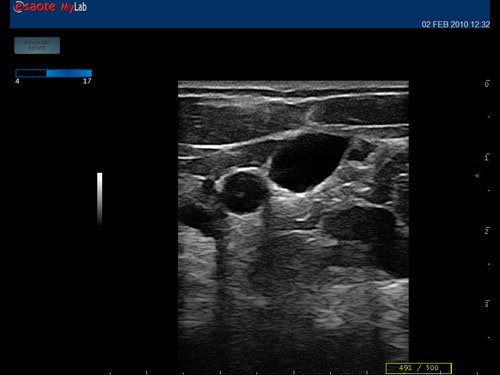

Das Ultraschallsystem MyLab™One zeigt exemplarisch den modernen Bedarf an Diagnosekapazitäten in verschiedenen Anwendungsbereichen: Radiologie, Kardiologie, Phlebologie, Frauenheilkunde, Orthopädie, Regionalanästhesie, Sportmedizin, Interventionell, Rheumatologie, Erste Hilfe, Notfallmedizin, Vaskuläre Reihenuntersuchungen, Allgemeinpraxis.

Kompromisslos für den Point-of-Care: konzipiert für Ihre Umgebung

Die kompromisslose Ausrichtung auf den Point-of-Care bedeutet Fokus und Achtung auf spezifische Anwendungen, um bestimmte technologische Entwicklungen zu nutzen, die die wirksamsten Lösungen bewirken. Das MyLab™One kombiniert leistungsstarke Software mit einer Bedieneroberfläche, die speziell auf die Anwendung abgestimmt ist, und einem umfassenden Zubehör, das das MyLab™One zu einem perfekten System für alle klinischen Umgebungen und Workflows macht.

• Features: Farb/Doppler, Nadelführung, SW/B-Bild